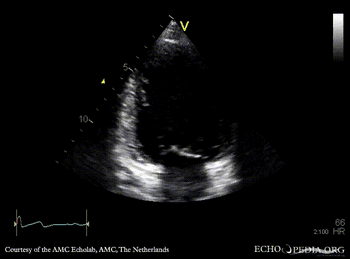

PLAX: Color Doppler, moderate mitral regurgitation A4CH: dilated poor left ventricle